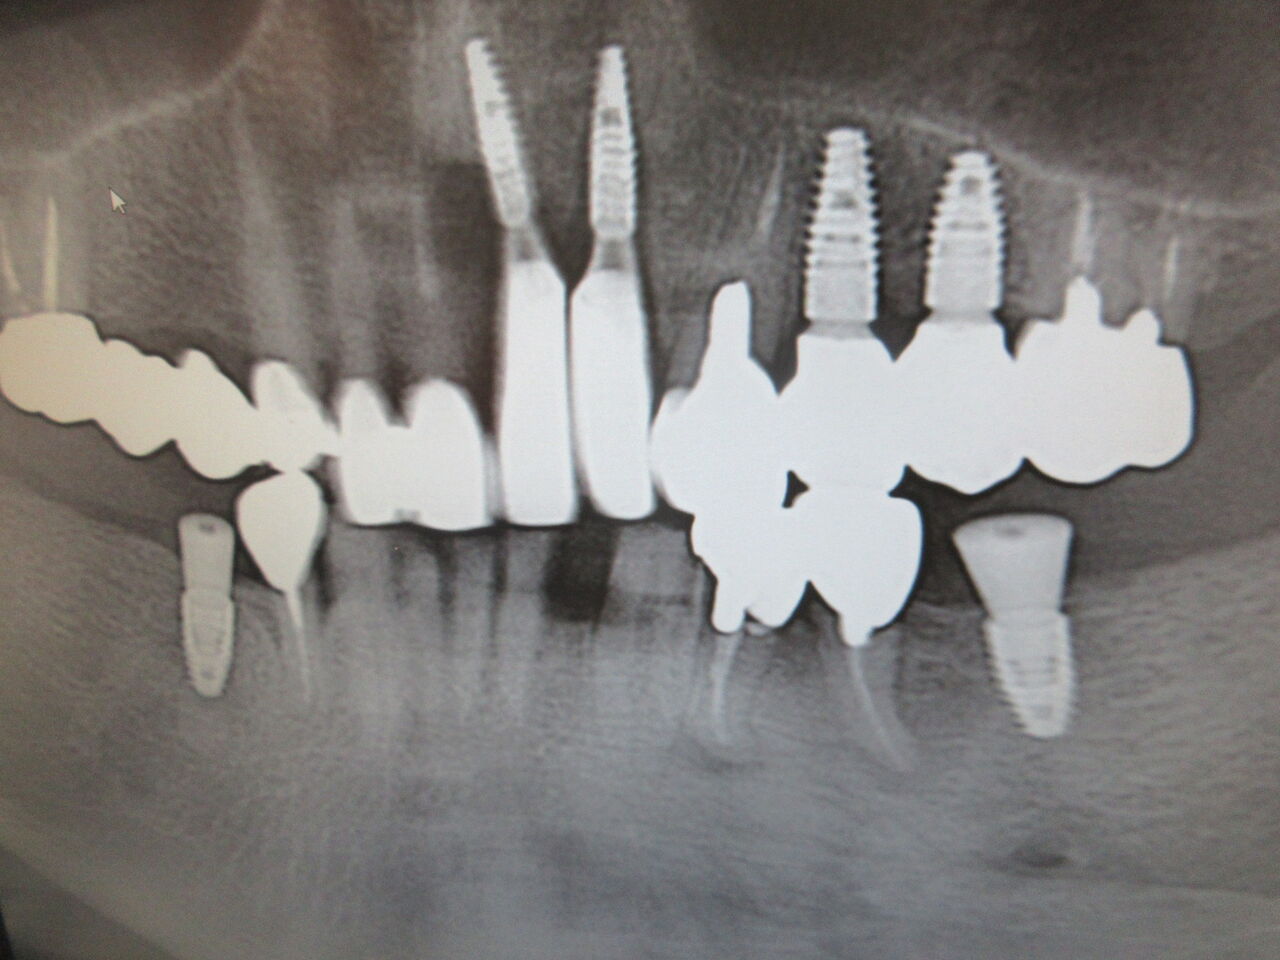

インプラントを埋入するケースはやはり健全な骨が必須です。下顎左側6番の埋入のケースですが手前の5番に大きな病巣があり、本来であれば、抜歯しなければケースでしたがお金も掛けられないということでそのままケースでしたがやはり抜けてしまいました。